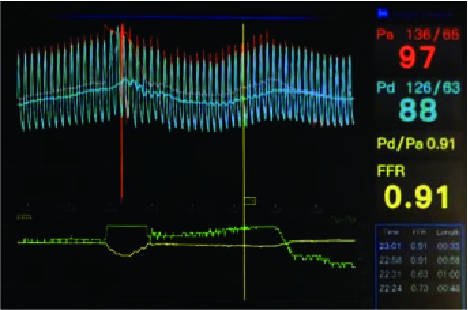

TruePhysio® pressure microcatheter followed the above workhorse wire and measured OM1 FFR as 0.91 (Fig. 2)

TruePhysio® pressure microcatheter was advanced to the distal D1 without any effort and given an FFR value of 0.90 (Fig. 5), with satisfactory angiographic results (Fig. 6)